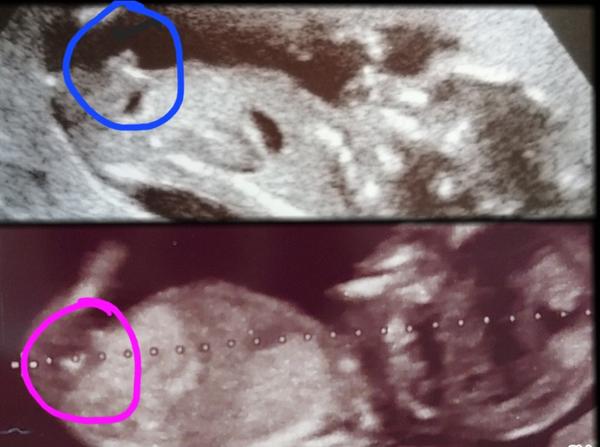

@anonym_autor podla nub theory si myslim,ze to ukazuje viac na dievcatko

@anonym_autor za mna podla nub theory skor chlapček … cakam teraz dievca a ten vybezok smeroval uplne rovno

@kendra73 ak môžem pridám sa aj ja. Čo myslite 🩵🩷? Čisto len zo zvedavosti🥹